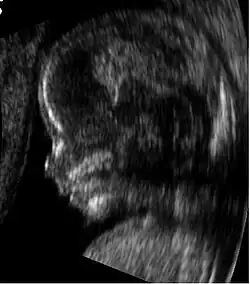

Profil d'un fœtus de 14 semaines